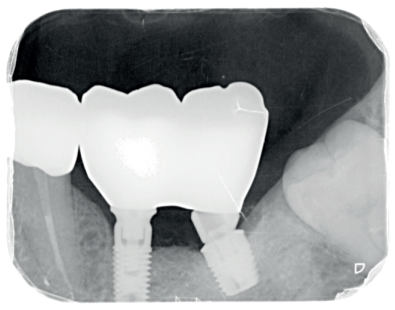

Pasados tres meses de la colocación de los implantes, se realizó un control clínico y radiográfico, se procedió a realizar la segunda fase y se derivó al Máster de Prótesis Bucofacial para continuar con el tratamiento. Se planificó el caso de manera totalmente digital. La arcada superior se rehabilitó con coronas de circonio, mientras que en la arcada inferior se realizaron coronas y puentes de circonio sobre implantes, incrustaciones de disilicato de litio y reconstrucciones de los bordes incisales inferiores con resinas compuestas (Figura 13).

En la revisión realizada a los seis meses, el paciente ha recuperado la función y la estética y está plenamente satisfecho con el resultado (Figura 14.) La radiografía periapical de control de los implantes cargados presenta buenos niveles óseos y una completa integración del injerto de dentina (Figura 15).